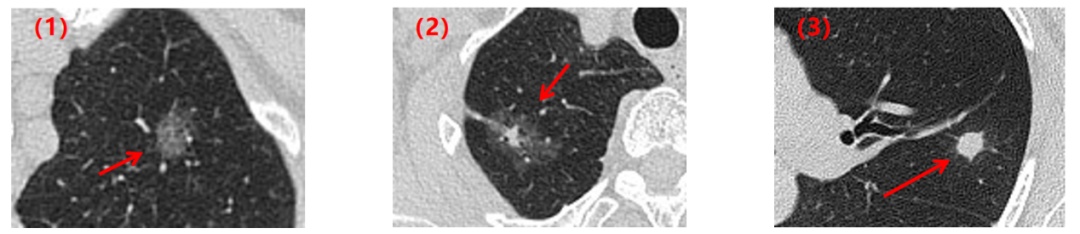

这是大家最关心的事了,我们来看几组肺结节随访病例模式图。

第一组:实性结节

患者1:2019年左肺发现一枚实性肺结节,两年后CT复查,肺内的这枚实性结节大小和形态没有明显变化。

患者2:2019年左肺发现一枚实性肺结节,两年的CT复查,肺内的这枚实性结节逐渐变小至消失不见了。

患者3:2016年右肺发现一枚实性肺结节,两年后复查CT,这枚结节明显增大,形态逐渐不规则,最后病理结果提示为肺癌。

第二组:磨玻璃结节

这是两例磨玻璃结节病例,肺结节既可以在三年的随访中保持不变,也可以在随访7个月后吸收消失了。

第三组:混杂磨玻璃结节

这是一例混杂磨玻璃结节,我们可以看到随着一次次的随访,结节的大小不断的增大,其中的实性成分也随之增多。该患者术后病理为肺癌。

所以,很显然,肺结节不等于肺癌。除了早期肺癌,肺部炎症、局灶性间质纤维化、出血等良性病变都可表现为磨玻璃结节。随访的结果决定了我们对“肺结节”的处理方式:继续随访、手术干预、或其他处理方式……

不同类型的肺结节的动态变化可以一样,也可以不一样,相同类型的肺结节也可以出现各种各样的变化,增大,缩小,或者是不变。这就是我们影像学上常说的同病异影,异病同影,影像学检查有其复杂性及局限性。所以,定期随访,动态观察更有助于影像诊断。